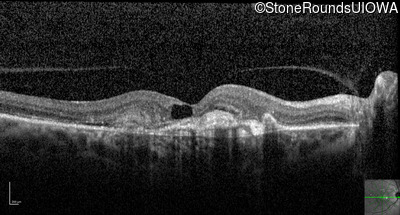

Optical Coherence Tomography - Right - 20/80 +1

Exemplar / OCT Stack